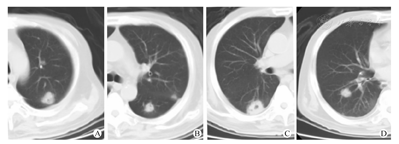

曲霉菌感染最常见的影像表现是多发大结节(图1),占75.8%,伴或不伴晕征(图2A),伴或不伴内部低密度及空洞(图2B),部分可见空气半月征。其他表现依次为实变(图2C、图2D)、肿块(图2E、图2F)、小结节及树芽征,大结节、实变及肿块可单独出现,小结节及树芽征多为伴随表现。出现胸腔积液的比例差异无统计学意义。

对几种主要病变的征象细节进行分析可以发现,以大结节为主要表现者,晕征、反晕征或病变内低密度、含气支气管征、空洞在两种感染中差异无统计学意义(P>0.05),体现空洞特点的内壁光滑与否,两种感染间差异无统计学意义(P>0.05)。表现为实变者,含气支气管征在细菌感染病例多见(P<0.05),空洞在曲霉菌感染多见(P<0.05),晕征、反晕征和病变内低密度影、胸膜下楔形实变两者比例差异无统计学意义(P>0.05)。表现为肿块者,曲霉菌感染病变多为单发(P<0.05),内容易看到空洞、空气新月征,但空洞内壁的光滑与否两者无区别(P>0.05)。晕征、含气支气管征、反晕征及病变内低密度的比例差异无统计学意义(P>0.05)。

本组所有曲霉菌感染病例中,与粒细胞缺乏患者曲霉菌感染相比[6],晕征出现的比例较低,占30.7%(表1)。